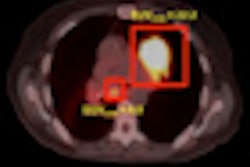

To determine metabolic response using FDG-PET, the group measured the maximum standardized uptake value (SUVmax) of the hepatic metastases. The researchers summed the SUVmax values for up to five of the most notable hepatic metastases, and they compared the percentage change on the follow-up scan versus the baseline results.

A decrease greater than 30% of the baseline SUVmax would indicate that a patient responded favorably to therapy. However, a decrease less than 30%, any increase in SUVmax, or the appearance of new hepatic lesions would be considered an unfavorable or lack of response to therapy.